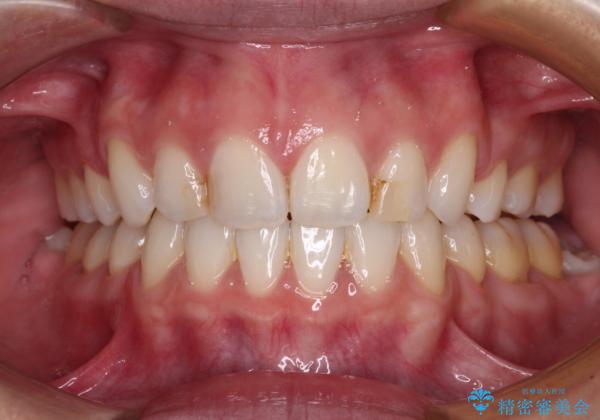

抜歯矯正を行ったことで、顎先のつっぱり感や口元の閉じにくさを解消することができました。